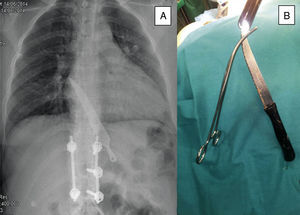

Entre sus antecedentes destaca un trastorno límite de personalidad con múltiples intentos de suicidio y artrodesis lumbar. La exploración física fue normal. Se efectuó una radiología simple de tórax (fig. 1A) que permitió observar un cuchillo situado a nivel del tercio inferior del esófago yuxta cardial, sin evidencia de neumotórax, neumomediastino ni neumoperitoneo. Se decidió la exploración bajo anestesia general, extrayendo el cuchillo, que media 22 cm, con la ayuda de un sobretubo endoscópico (fig. 1B)

La endoscopia flexible bajo anestesia general y con supervisión de cirugía es una herramienta que se ha de tener en cuenta para la extracción de cuerpos extraños intestinales.